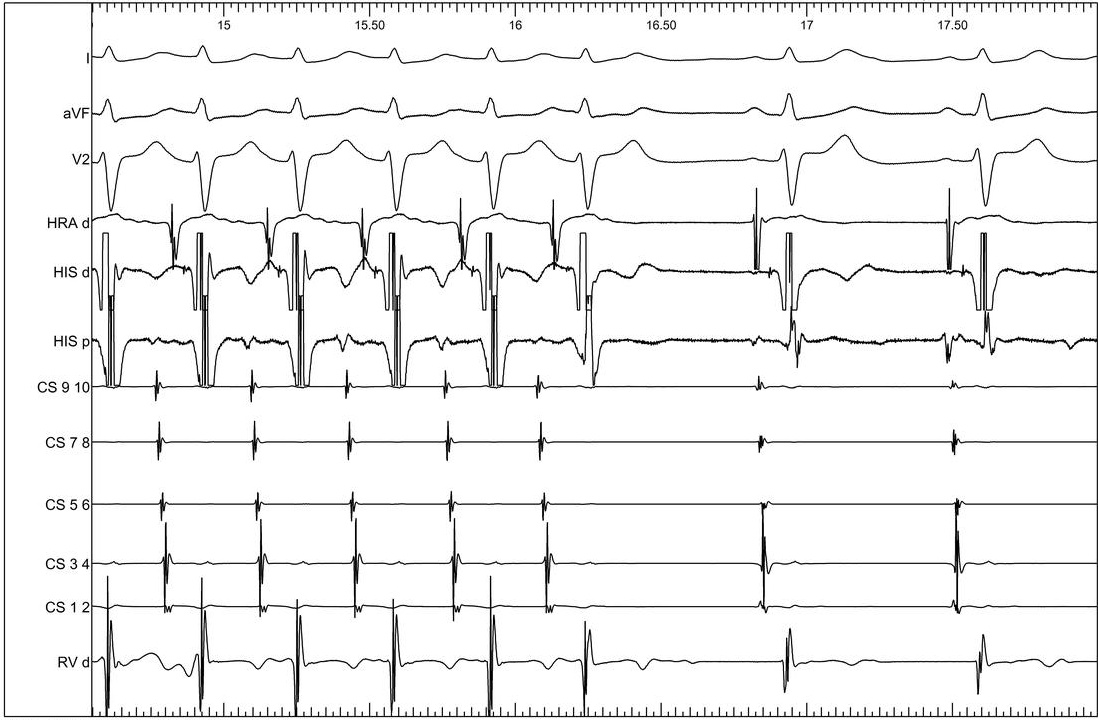

Atrial incremental pacing

03_avwb.jpg